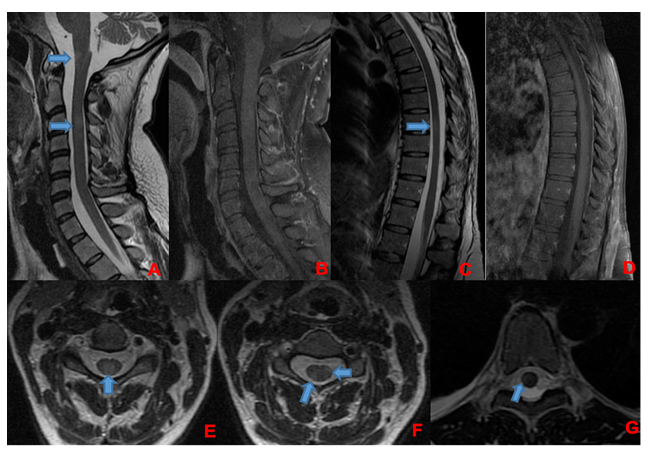

A 35-week pregnant woman was diagnosed with dengue fever. Within three days, she developed confusion and seizures, requiring emergency caesarean section and mechanical ventilation. Brain computed tomography revealed a hypodense lesion in the left temporal lobe with mass effect compatible with limbic encephalitis (Figure 1). Cerebrospinal fluid (CSF) analysis showed 40 cells/mm³ and 80 mg/dL of protein. Empirical intravenous acyclovir (10 mg/kg every 8 h) was initiated because of the presumptive diagnosis of herpetic encephalitis. After 9 d, she was extubated but remained cognitively impaired and was discharged 11 d later with partial neurological recovery. Two days later, she was admitted to a tertiary referral hospital with fever and generalized weakness. Brain magnetic resonance imaging (MRI) demonstrated the involvement of limbic structures, hyperintensities in the cortical and subcortical brain parenchyma with subtle mass effects, cortical enhancement in these regions, and findings consistent with volume loss in the left mesial temporal lobe and insular cortex, likely resulting from previous encephalitis (Figure 2). MRI revealed demyelinating lesions in the cervical and thoracic spinal cord (Figure 3). CSF analysis showed 57 cells/mm³, more than 300 mg/dL protein, and glucose of 42 mg/dL. Molecular tests, including those for dengue and herpesviruses, as well as metagenomic sequencing of CSF, were negative. A comprehensive panel for autoimmune encephalitis in both the blood and CSF also yielded negative results. She received pulse methylprednisolone for 5 d, followed by intravenous immunoglobulin for 5 d, with slight cognitive improvement.

FIGURE 3: Corresponding spinal cord images of MRI showed in Figure 2. Demyelinating lesions in cervical (A, B, E, and F) and thoracic spinal cord (C, D, and G). In A and B, sagittal plane of cervical spinal cord, showing lesions in T2-weighted image (A) without enhancement in T1 post-gadolinium (B). There are involvement of spinal cord grey matter (E) and white matter (F) as show in axial T2-weighted images. In C and D, sagittal plane of thoracic spinal cord, showing one lesion in T2-weighted image (C) without enhancement in T1 post-gadolinium (D). This lesion was located in spinal cord white matter as shown in axial T2-weighted image in that level (G). Demyelinating lesions are indicated by blue arrows.